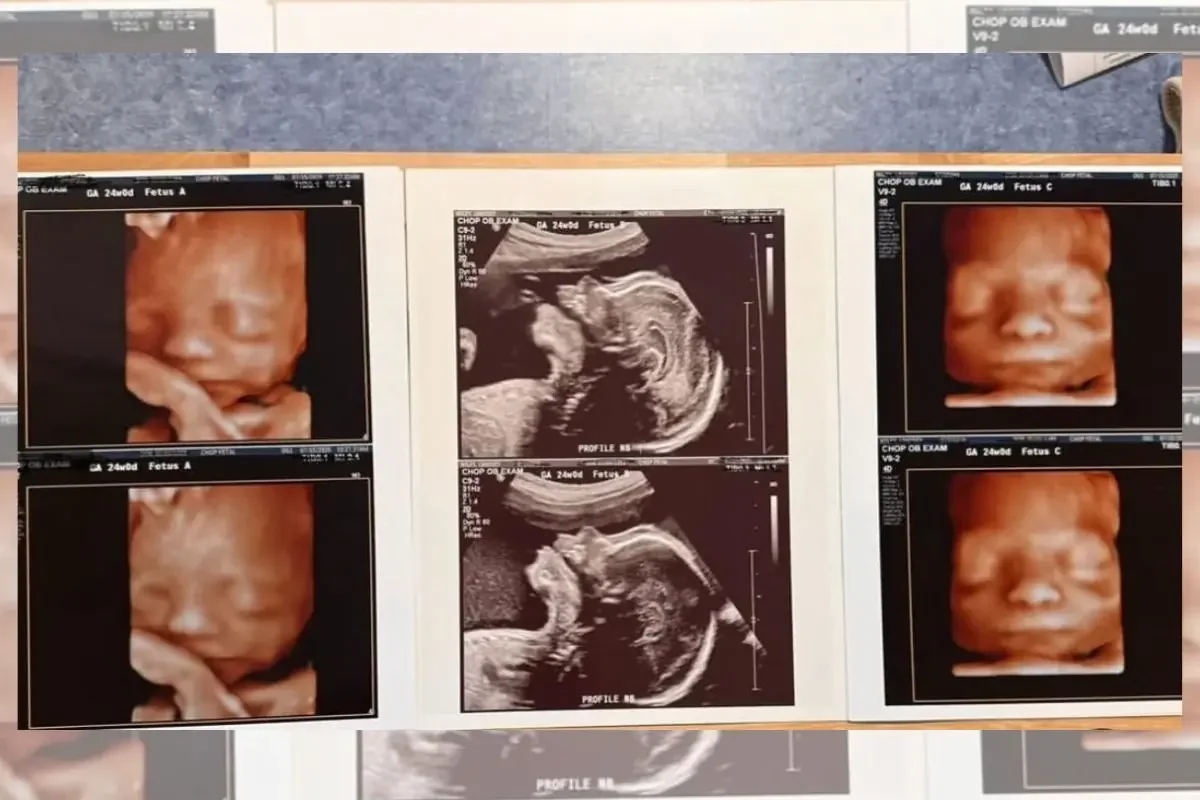

Lindsey Wiley, una madre estadounidense de 32 años y residente en Estados Unidos, vivió una sorprendente vuelta del destino. Con tres hijos varones de 5, 3 y 1 año y medio, ella y su pareja decidieron intentar una última vez ampliar la familia con la esperanza de tener una niña. Sin embargo, durante la primera ecografía, recibieron una noticia totalmente inesperada: estaban esperando trillizos, y todos eran niños.

El impacto fue inmediato. Lindsey confesó haber sentido miedo y sorpresa ante el diagnóstico. Lo que comenzó como un plan para cerrar el ciclo de embarazos con una hija, se transformó en una aventura que multiplicó por dos el número de hijos esperados. La pareja pasará de tener tres a seis hijos, lo que ha generado una mezcla de emociones: alegría, ansiedad, nostalgia y una gran sensación de responsabilidad.